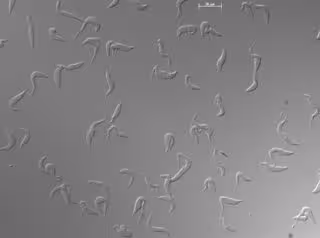

Archivo - Células de ‘Trypanosoma brucei’ en cultivo observadas al microscopio. /

Archivo - Células de ‘Trypanosoma brucei’ en cultivo observadas al microscopio. / - IPBLN-CSIC - Archivo

La TAH es una enfermedad transmitida por vectores causada por el parásito sanguíneo 'Trypanosoma brucei'. Se transmite a los humanos por la picadura de moscas tsé-tsé infectadas por el parásito de humanos o animales infectados. Las poblaciones rurales que dependen de la agricultura, la pesca, la ganadería o la caza son las que corren mayor riesgo de exposición.